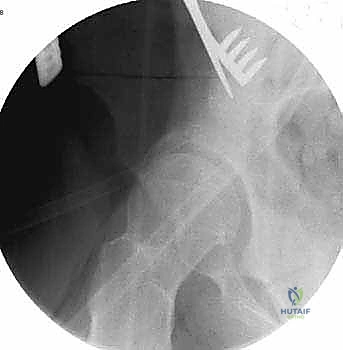

تُعد هذه الجراحة سيمفونية من الدقة الجراحية. تستغرق العملية عادة من 2 إلى 4 ساعات، وتتم تحت التخدير العام أو النصفي المتقدم مع التحكم في الألم (Epidural). إليك تفصيل للخطوات الميكانيكية الدقيقة التي ينفذها الأستاذ الدكتور محمد هطيف باحترافية عالية:

2. سلسلة قطع العظام (The 5 Osteotomies)

يكمن سر نجاح جراحة PAO في إجراء خمسة قطوع عظمية منفصلة حول الحُق، لتحريره بالكامل عن باقي الحوض، مع ترك العمود الخلفي سليماً كدعامة أساسية.

القطع الأول: القطع الإسكي غير المكتمل (Incomplete Ischial Osteotomy)

باستخدام إزميل خاص ذو زاوية (Angled Osteotome)، يتم إجراء قطع في عظم الإسك أسفل الحُق مباشرة (في الأخدود تحت الحُقي). يتم هذا القطع بتوجيه الأشعة السينية (Fluoroscopy) لضمان عدم اختراق المفصل. يحرص الدكتور هطيف على إبعاد العصب الوركي والأوعية السدادية بأمان تام.